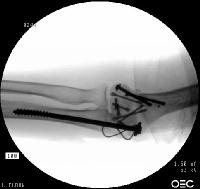

Open reduction via olecranon osteotomy.  The ulnar nerve is  retracted with a penrose drain. The articular surface was reconstructed, then secured to the shaft. After recovering the rotated anterior articular fragment, the anterior and posterior halves of the central articular component were secured with .062" pins. These pins were replaced one at a time with Herbert screws.

Later in the case, the small medial osteochondral fragment was secured with absorbable sutures (not shown).

In similar steps, the reconstructed central articular component was secured to the proximal humerus with pins. Once satisfactory reduction was obtained (not yet, as seen here...), the pins were replaced by more Herbert screws. This allowed fixation of the purely osteochondral segments without prominent harware.